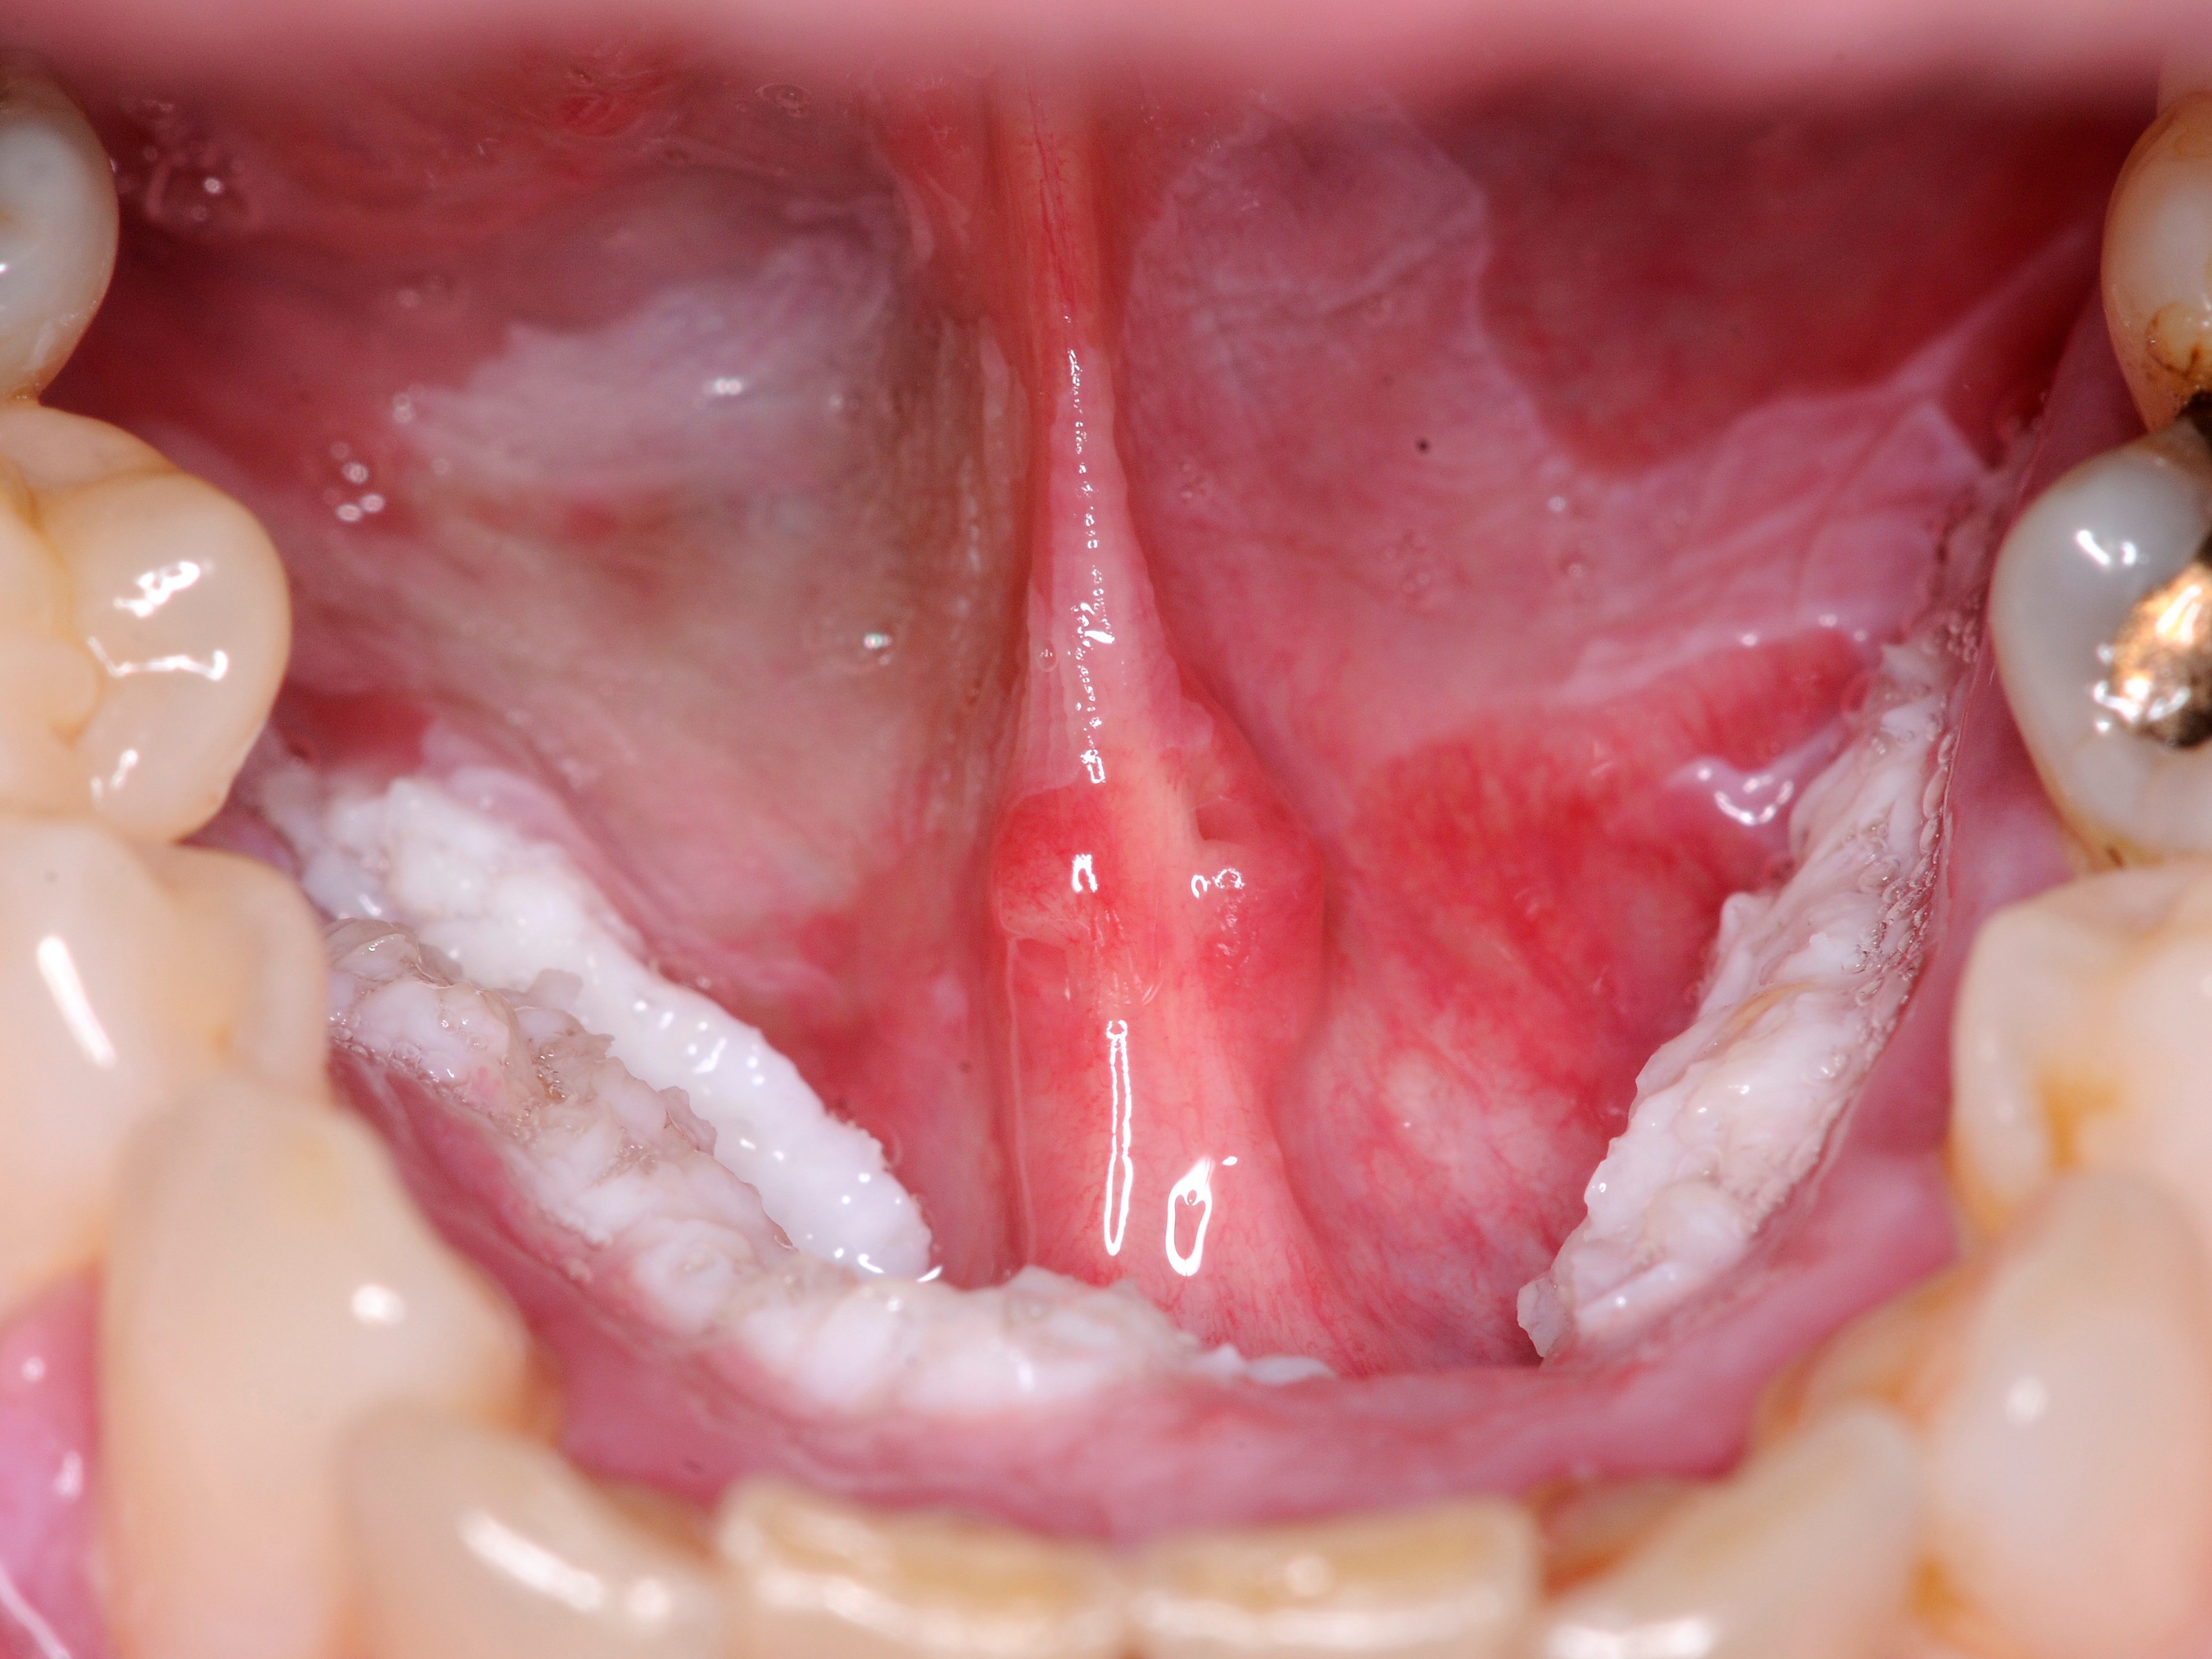

Orale floride papillomatose (oral florid papillomatosis) is een verruceus carcinoom van de mondholte. Het kan ook elders in de nasopharynx zitten. Het wordt ook wel een Ackerman tumor genoemd naar de patholoog Ackerman. De tumor gedraagt zich niet als een echt carcinoom. Het is een weinig agressief goed gedifferentieerd plaveiselcelcarcinoom. Sommigen beschouwen het als een soort overgangsstadium tussen een virale wrat en een verruceus carcinoom. Maar omdat ze erg groot kunnen worden veroorzaken ze wel klachten en schade. Het is een zeldzame aandoening, vooral voorkomend bij ouderen (> 60 jr), meer bij mannen dan bij vrouwen. De term orale papillomatose zonder de toevoeging floride wordt gebruikt voor gewone door HPV virus geïnduceerde wratten van de mondholte. Multipele orale papillomen worden ook gezien bij Heck disease (focale epitheliale hyperplasie).

Histologisch gaat het om goed gedifferentieerde plaveiselcelcarcinomen met een verruceuze architectuur. De tumoren groeien langzaam, zijn wel lokaal invasief en verdringend, metastaseren zelden. Er worden twee belangrijke oorzaken genoemd: HPV infectie (humaan papilloma virus) en roken, en nog vaker het pruimen (kauwen) van tabak wat in grote delen van de wereld nog gedaan wordt.